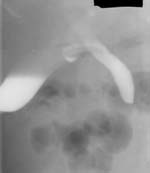

3. Больной М., 58 лет, находился в хирургии с механической желтухой, обусловленной

наличием конкремента в терминальном отделе общего желчного протока. С целью

разгрузки желчных путей была установлена дренажная трубка в желчном пузыре.

Врачами было предложено извлечение конкремента с помощью фибродуоденоскопа через

сфинктер Одди. Предварительно была произведена чрезпузырная холлангиография

с водорастворимым контрастным веществом и релаксационная дуоденография с барием

с целью уточнения локализации конкремента. На произведенной рентгенограмме конкремент

расположен в 2 см от сфинктера Одди. Полученная информация изменила тактику

лечения (Рис. 3).

Рис. 3. При заполнении желчных протоков определяется обтурация

желчного протока конкрементом (Слева). При контрастировании

желудка и 12-перстной кишки определено расстояние между уровнем

обтурации и сфинктером Одди (Справа).